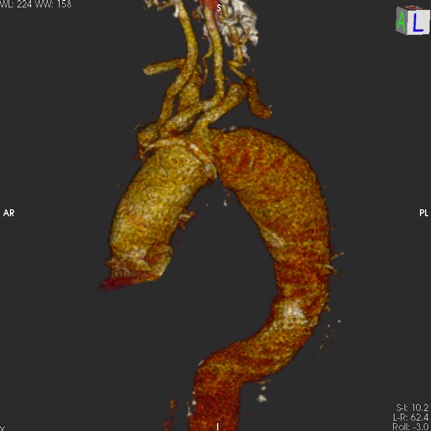

Przeprowadzony 27 lipca 2021 r. zabieg wykonano u 71-letniej pacjentki z rozwarstwieniem łuku aorty i tętniakowatym poszerzeniem kanału fałszywego, po przebytej operacji wymiany aorty wstępującej w 2011 r. z powodu ostrego rozwarstwienia aorty typu A. Chora nie została zakwalifikowana do ponownej operacji otwartej z użyciem krążenia pozaustrojowego (ang. extracorporeal circulation – ECC).

Całą procedurę implantacji stentgraftów i fenestracji poprzedzono wykonaniem angiograficznej próby okluzyjnej, oceniającej wydolność koła tętniczego mózgu przy czasowo zamkniętej lewej tętnicy szyjnej wspólnej. Ponadto, do monitoringu przepływów domózgowych wykorzystano ciągły, przezczaszkowy pomiar oksymetrii półkul mózgu (NIRS).

Przy użyciu lasera eksimerowego z przezskórnych dostępów naczyniowych (nakłucie igłą) przez lewą tętnicę szyjną wspólną oraz lewą tętnicę podobojczykową wykonano fenestrację poszycia implantowanego jednoczasowo stentgraftu, a następnie przez powstałe otwory, przy użyciu stentów krytych zaopatrzono powyższe naczynia, uzyskując przepływ przez wszystkie gałęzie łuku aorty.

Operacja odbyła się bez powikłań. Zarówno kontrolna arteriografia, jak i angio-TK po zabiegu wykazały wyłączenie z układu krążenia rozwarstwienia w obrębie łuku aorty oraz prawidłowy przepływ krwi w tętnicach domózgowych.